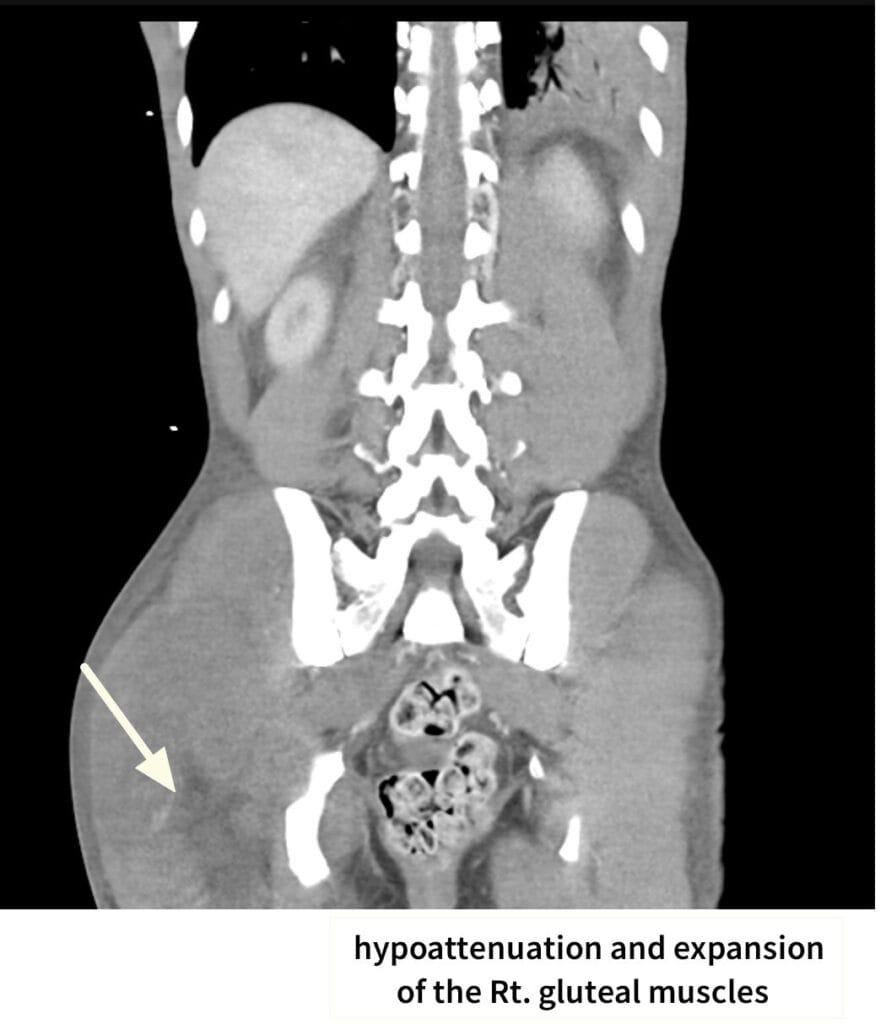

– ANCA 관련 혈관염: 육아종증(polyangiitis), 현미경적 다발혈관염(MPA), 호산구성 육아종증 혈관염(EGPA)

– Anti-GBM 병: 굿파스처 증후군(폐출혈 + 신부전)

– 전신질환: SLE, 혈전성 미세혈관병증(TMA) 일부도 포함

[임상양상]

– 혈뇨·단백뇨

– 고혈압·부종

– 전신 증상: 발열, 체중 감소, 피부 발진, 폐출혈(특히 Anti-GBM)

– 신기능이 수일~수주 내 급격히 악화됩니다.